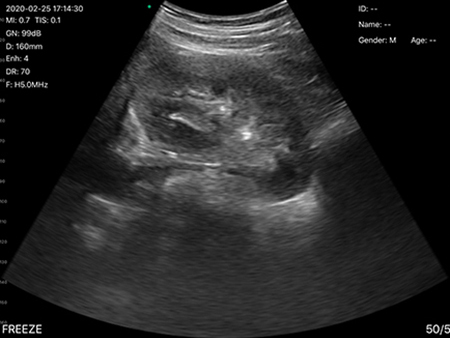

- Abdomen